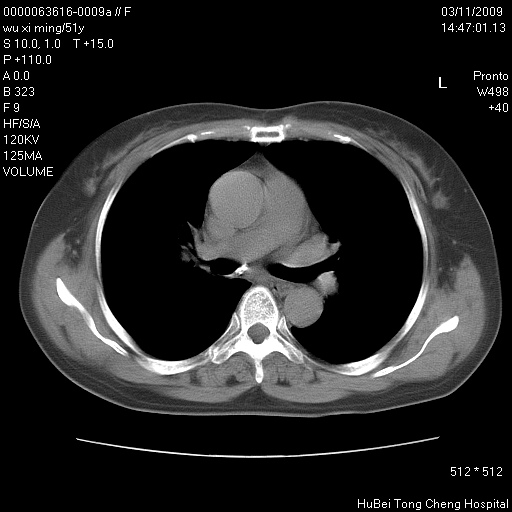

患者 女,51岁。因“胆囊炎,胆囊结石”,行常规术前胸部x线检查发现:右上肺结节病灶,建议行进一步检查。患者无咳嗽、咳痰及咯血等呼吸道症状,近期出现背部疼痛不适。

胸部ct轴位平扫(层厚10mm,螺距1.5,重建间隔10mm;部分层面:层厚3mm,螺距1.0,重建间隔3mm),图像如下:

考虑右肺癌肺内转移!

右肺周围型肺癌伴肺内转移信胸椎转移

1、周围型肺癌。(毛刺正、血管束集征,分叶。)

支持--右肺周围型肺癌---胸椎转移

集束征,胸膜牽拉征,毛刺,淺分葉高度提示ca.

右肺周围型肺癌伴肺内转移及胸椎转移。已无手术机会。